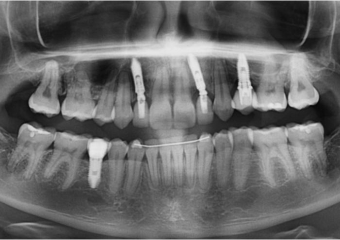

Raio X inicial